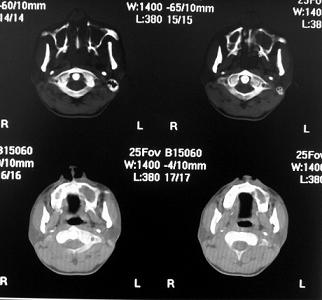

考虑慢性副鼻窦炎合并双侧鼻腔息肉

同意鼻息肉伴双侧付鼻窦炎